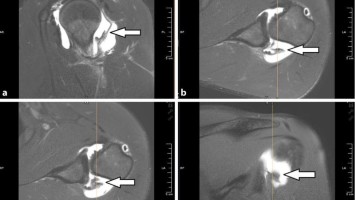

Ein 18-jähriger athletischer Rechtshänder stellte sich aufgrund einer progredienten Instabilitätssymptomatik der adominanten Schulter vor. Dabei berichtete er von multiplen Subluxationsereignissen und einigen kompletten Auskugelungen in eine angedeutete „Erecta“-Stellung, die der Patient selbst reponieren konnte. Konventionell radiologisch war alles unauffällig. Der MR-tomographische Befund durch die Artho-MRT-Untersuchung widersprach jedoch diesem Eindruck.